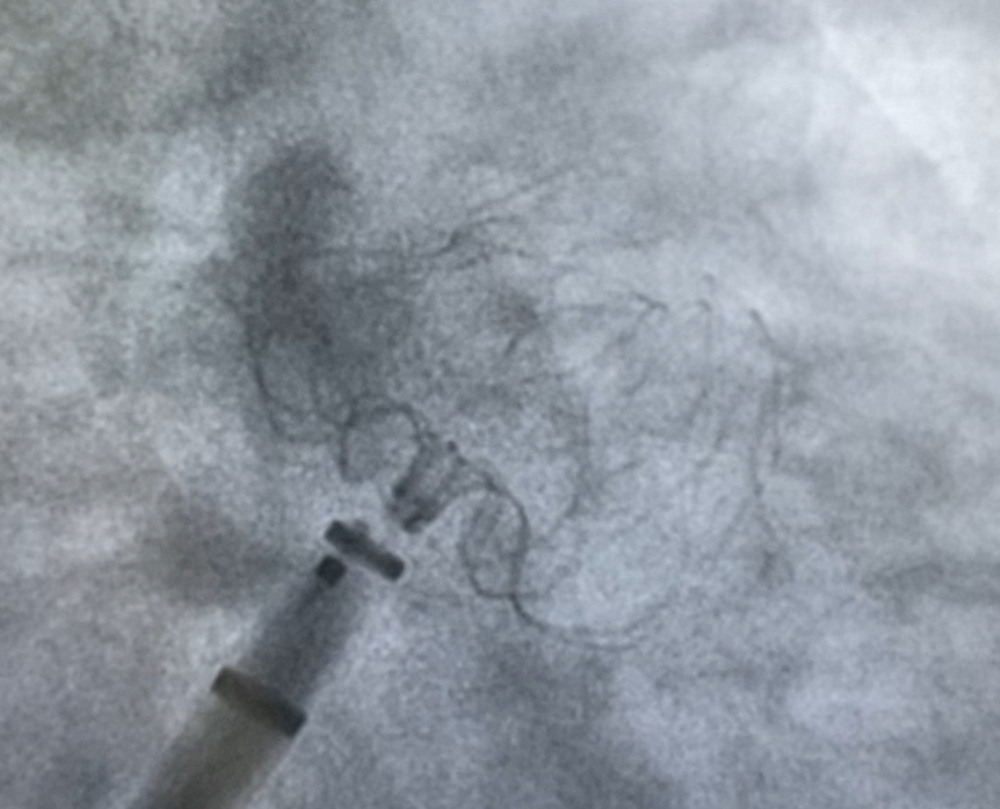

术中DSA影像图

经过充分的病情沟通后,手术团队成功为患者实施冷冻球囊消融联合左心耳封堵术的“一站式”治疗,为患者成功解决困扰多年的房颤问题和因房颤可能导致的其他并发症。